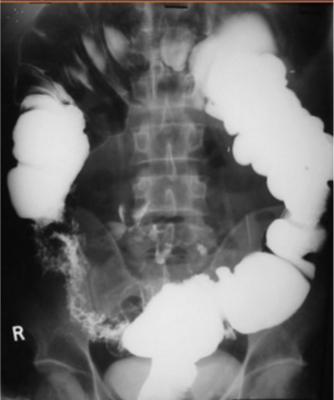

Image radiologique de lavement baryte

tuberculose ileo-caecale est :

- Au stade aigue et subaigue , c'est :

Lesion ulceree a la region ileo coecale - Epaisissement et

angulation de la valvule ileocaecale ( signe de

Fleischner) , Stenose de ileon terminale , Hypermobilite du caecum |

- Au stade chronique : la valvule

ileoceacale est fixe , rigidite et imcompetance , la

ceacum est en aspect conique et diminue sa taille .

Aspect

deformation de la region ileocaecale avec

retrecissement de ileon . Image radiologique de

lavement baryte mono de contrast |

Image de retrecissement et deformation de

la region ileo-caecale . La valvule ileocaecale est

fixe , rigidite et incompetance . Tuberculose

ileocaecale . Image radiologique en mono de contrast

Image de lavement baryte en double de contrast :

Tuberculose ileo-caecale avec image de ileon tres

deforme , bord irregulier , angulation et stenosante

. |

Tuberculose ileo-caecale : image de

deformation en conique du caecum . Ileon est

irregulie et stenosante . Image de lavement baryte

mono de contrast . |